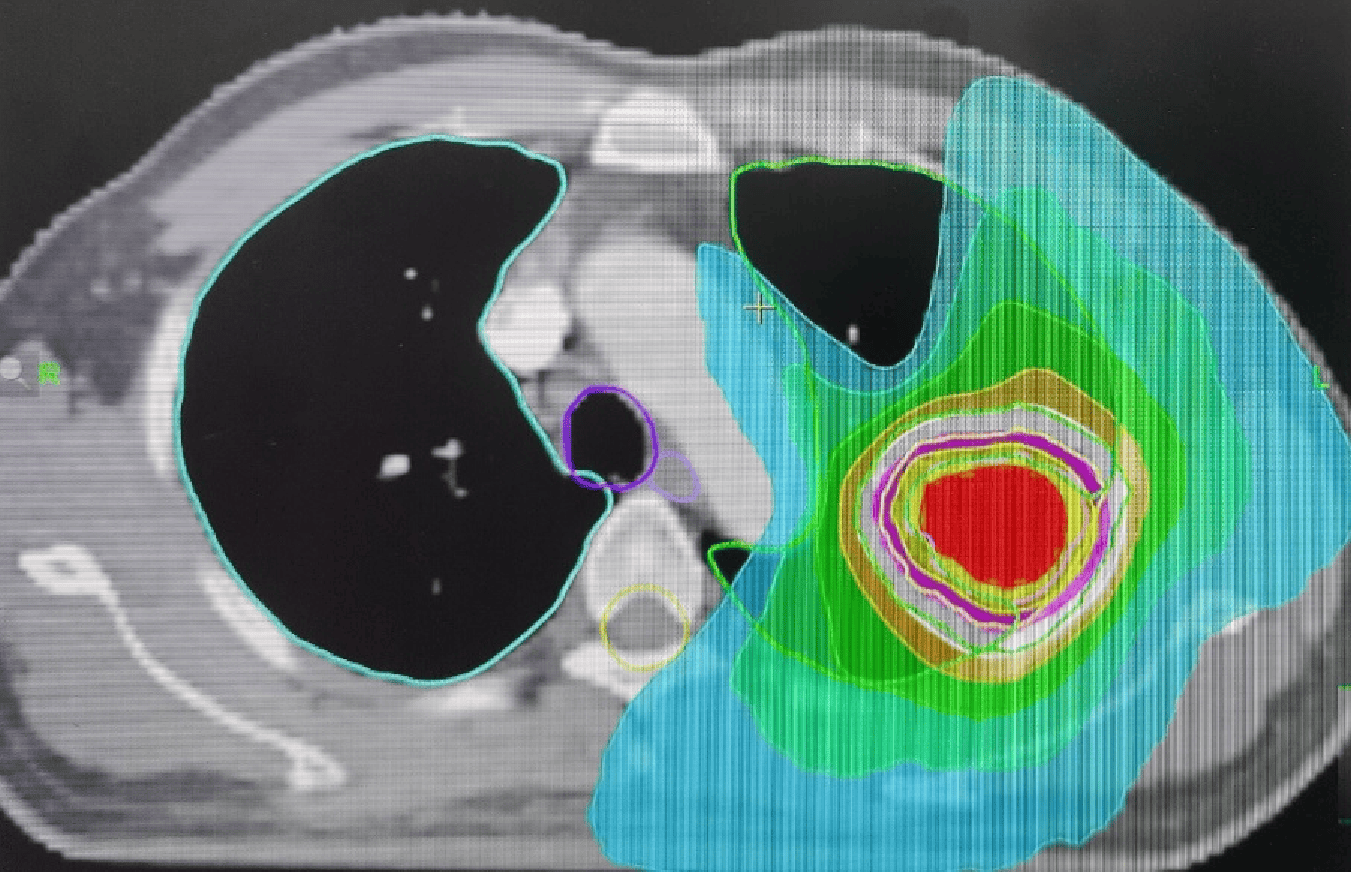

在核工业四一六医院见到夏廷毅教授,他说:“你的情况手术风险极大,但这个小病灶用放射外科解决易如反掌,通过聚焦核能射线,直接让癌细胞死亡,治疗过程没有器官的毁损,你有基础病也能承受。”

治疗后复查,肿瘤从明显缩小到最终变为瘢痕。两年过去,瘢痕几乎隐匿不见,我也早已回归了散步、喝茶的平凡日常。